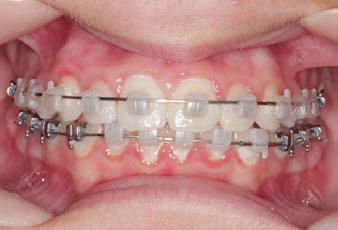

CLASS II DIV.1 - Marra

INITIAL - 4/4/18

PROGRESS 1 - 26/9/18 - Class I platform accomplished in 5.75 months with Motion 3D COLOR Appliance

PROGRESS 2 - 26/9/18 - Placement of the SLX 3D Clear Brackets